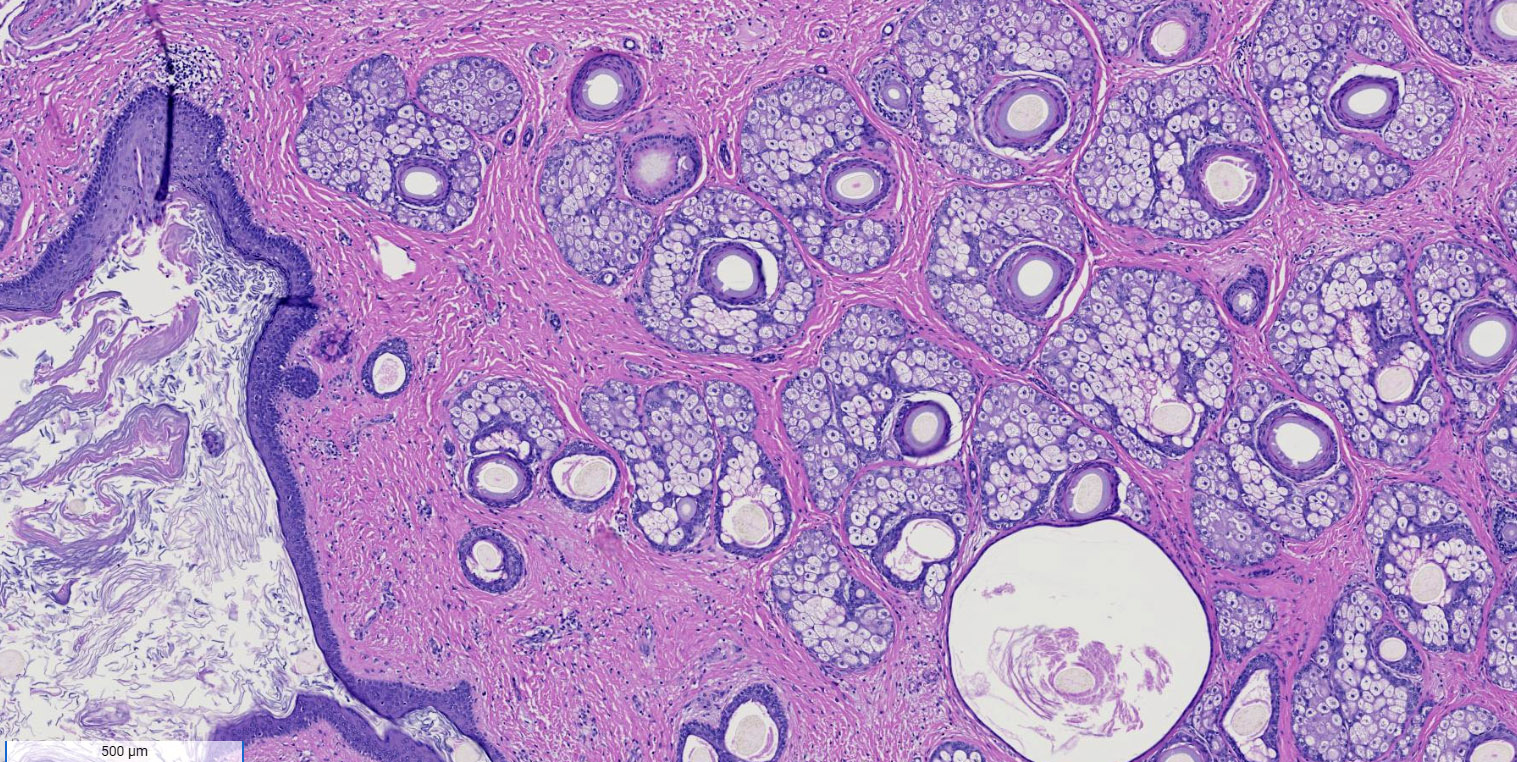

Microscopic (histologic) description

- Mixture of mature, benign tissues

- Ectodermal (most common): squamous epithelium, sebaceous glands, hair follicles, brain tissue

- Mesodermal (second most common): bone, cartilage, smooth muscle, fibroadipose tissue

- Endodermal: intestinal or respiratory epithelium, thyroid, salivary gland

- Microscopic foci of immature neuroepithelium (less than or equal to 4 foci or 21 mm2) does not warrant diagnosis of immature teratoma and will not affect prognosis (Int J Gynecol Pathol 1987;6:203)

- Fat necrosis and foreign body reaction may be seen

Microscopic (histologic) images